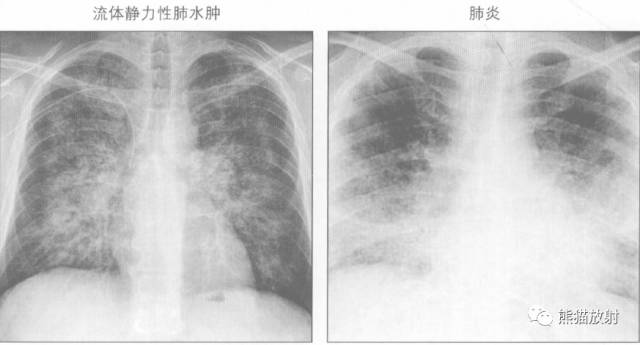

鉴别诊断

蝙蝠翼样肺部影可由以下原因引起:

↓ Pulmonary oedema 肺水肿

↓ 卡氏肺囊虫肺炎